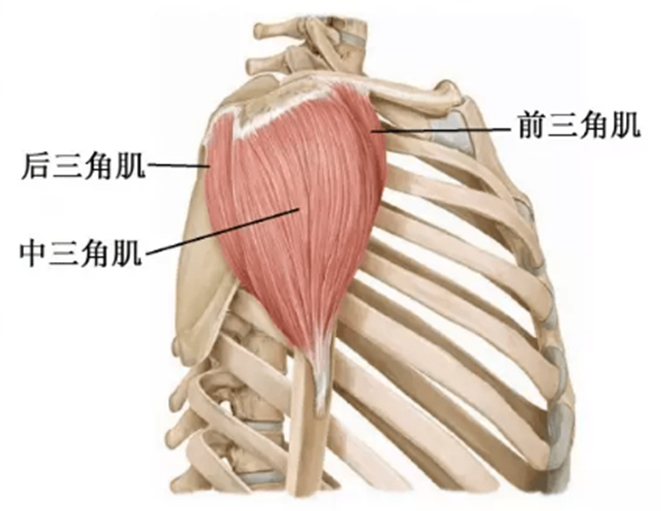

肩关节周围肌群

三角肌:起自锁骨外1/3、肩峰、肩胛冈,由三束组成,止于肱骨三角肌粗隆,由腋神经(C5—7)支配。作用:使肩关节外展、后伸和旋外、前屈和旋内。

1、前屈:肩关节前屈主要由三角肌前部纤维、胸大肌锁骨部、喙肱肌、肱二头肌完成,其中三角肌前部纤维最明显。

2、后伸:肩关节后伸的肌肉主要有三角肌后部纤维、背阔肌、胸大肌的胸肋部、大圆肌和肱三头肌长头,其中三角肌后部纤维作用最大。

3、内收:主要有胸大肌、大圆肌、背阔肌、喙肱肌、肱二头肌长头,此外三角肌前后部纤维也有内收作用。

4、外展:肩关节的外展由三角肌(主要是其中间束)及冈上肌完成。当肩处于内旋或外旋位置时,三角肌在最外侧的部分是外展的主要肌肉,当肩外旋时外展肌力要更强些。

5、内旋:内旋肌主要是肩胛下肌,当肩关节处于特定体位时胸大肌三角肌前部纤维、大圆肌及背阔肌也有一定的内旋作用。

6、外旋:肩关节的外旋肌有冈下肌、小圆肌及三角肌后部纤维。